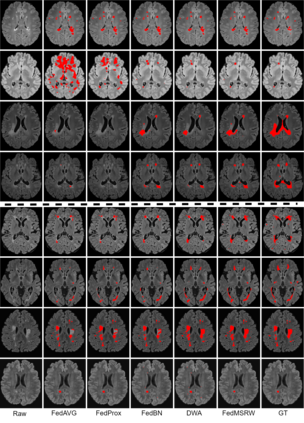

Federated learning (FL) has been widely employed for medical image analysis to facilitate multi-client collaborative learning without sharing raw data. Despite great success, FL's performance is limited for multiple sclerosis (MS) lesion segmentation tasks, due to variance in lesion characteristics imparted by different scanners and acquisition parameters. In this work, we propose the first FL MS lesion segmentation framework via two effective re-weighting mechanisms. Specifically, a learnable weight is assigned to each local node during the aggregation process, based on its segmentation performance. In addition, the segmentation loss function in each client is also re-weighted according to the lesion volume for the data during training. Comparison experiments on two FL MS segmentation scenarios using public and clinical datasets have demonstrated the effectiveness of the proposed method by outperforming other FL methods significantly. Furthermore, the segmentation performance of FL incorporating our proposed aggregation mechanism can exceed centralised training with all the raw data. The extensive evaluation also indicated the superiority of our method when estimating brain volume differences estimation after lesion inpainting.